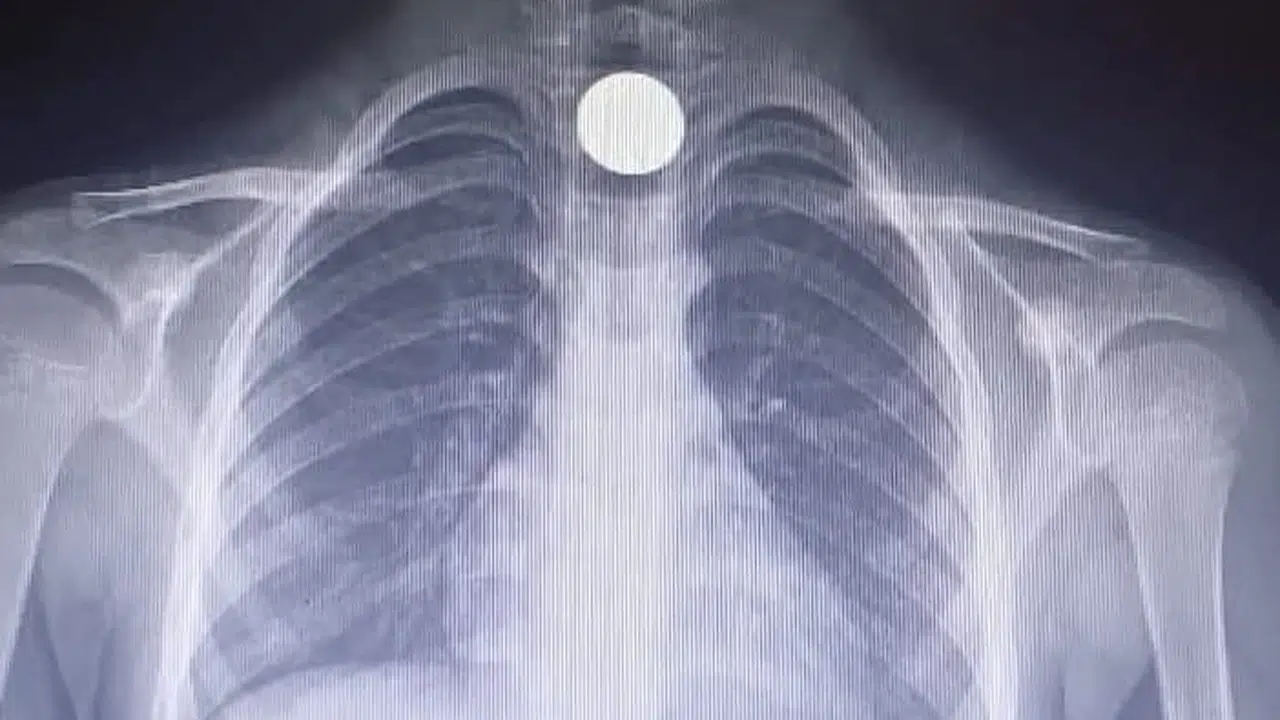

Yavuz YILMAZ/İNEGÖL (Bursa), (DHA)-BURSA'nın İnegöl ilçesinde Yusuf Z.'nin (5) yemek borusuna takılan madeni para, operasyonla çıkartıldı.

Olay, saat 14.00 sıralarında İnegöl ilçesi Mesudiye Mahallesi'nde meydana geldi. Sarmaşık Sokak'taki evlerinde oynayan Yusuf Z., fenalaşınca ailesi tarafından özel otomobille İnegöl Devlet Hastanesi'ne götürüldü. Tetkiklerde, yemek borusuna 50 kuruşluk madeni para kaçtığı tespit edilen Yusuf Z., ambulansla Bursa Yüksek İhtisas Eğitim ve Araştırma Hastanesi'ne sevk edildi. Yusuf Z.'nin yemek borusundaki para, burada yapılan başarılı ameliyatla çıkartıldı. (DHA)